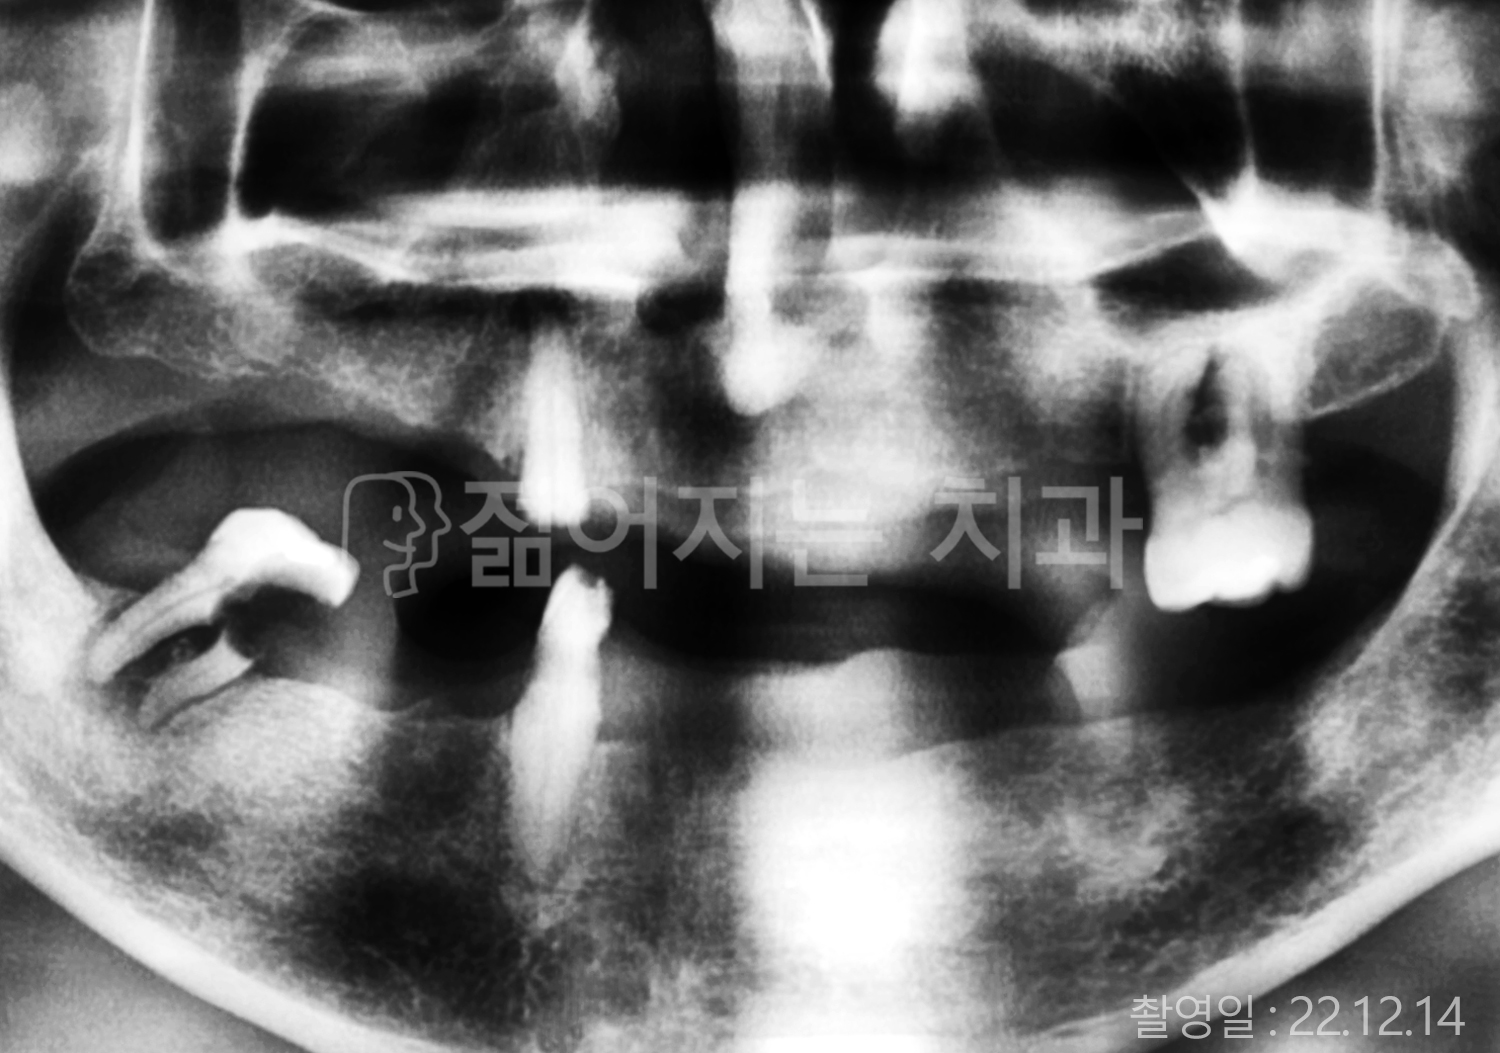

• 40대 전체치아 10개 이상 임플란트

• 70대 당뇨 전체치아 10개 이상 임플란트

• 60대 전체치아 10개 이상 임플란트

• 60대 고혈압, 당뇨, 고지혈증 전체치아 10개 이상 임플란트

• 50대 전체치아 10개 이상 임플란트

• 70대 고혈압, 당뇨 전체치아 10개 이상 임플란트

• 60대 고혈압 전체치아 10개 이상 임플란트

• 50대 고혈압, 당뇨, 고지혈증 전체치아 10개 이상 임플란트

• 60대 고혈압, 고지혈증 전체치아 10개 이상 임플란트